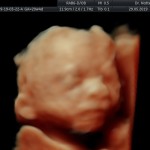

Modalidad de imagen ecográfica que permite evaluar, medir y capturar estructuras fetales superficiales e internas en 3 dimensiones (3D) y también en movimiento y en tiempo real (4D) con programas de realismo aumentado (HD LIVE) e imágenes tomografías fetales (TUI) mejorando significativamente la precisión en las mediciones fetales y la documentaciones de estructuras anatómicas.

Esta tecnología se puede utilizar desde la 6ta a la 40ma semana de embarazo.